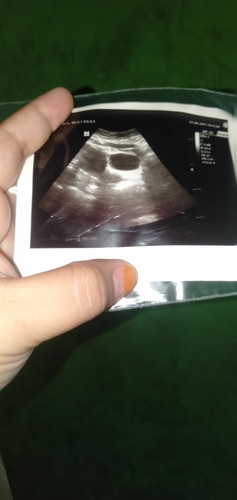

ini usg perut ya bund? ga coba usg transvaginal? 6w wajar aja kalo masih penebalan rahim/baru terlihat kantung janin, biasanya dokter akan suruh balik 2-3 minggu lagi. rata2 janin terlihatnya di 8-10w, ada sih yg sblm itu jg udh terlihat tp beda2 antar ibu hamil satu dg yg lainnya